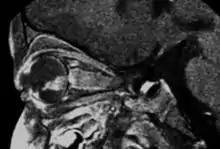

Sagital MRI

- MRI: assessment of local extension to optic nerve, anterior chamber, and orbital fat. Slightly hyperintense on T1, hypointense on T2. Also to rule out trilateral retinoblastoma

- If patients needs enucleation, consider systemic staging with CSF cytology, bone marrow cytology, and spinal axis MRI